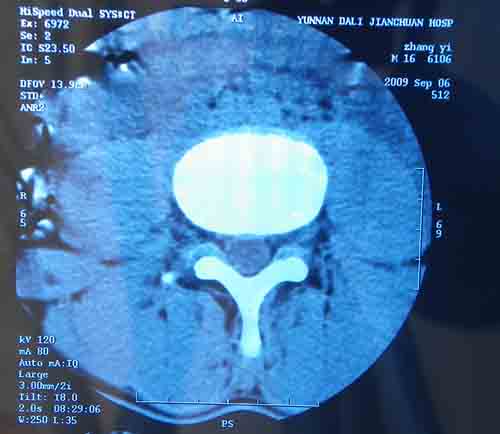

腰5/骶1椎间膨突出外,还有点异常,不知是什么东东,请各位大虾帮忙看看(12骨窗最明显)

椎体后缘软骨结节

软骨结节

支持 椎体后缘软骨结节。